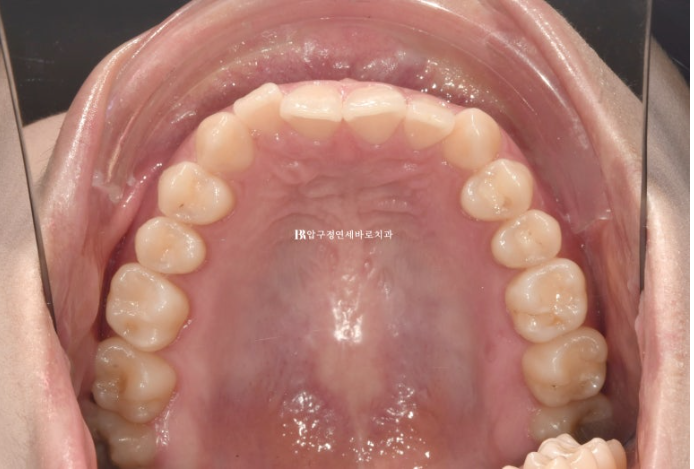

24.02~24.11

뒤로 쓰러져 있던 앞니가 나오면서 악궁모양이 네모진 형태에서 원형으로 바뀌었습니다.

아래 악궁모양이 좋아졌습니다.